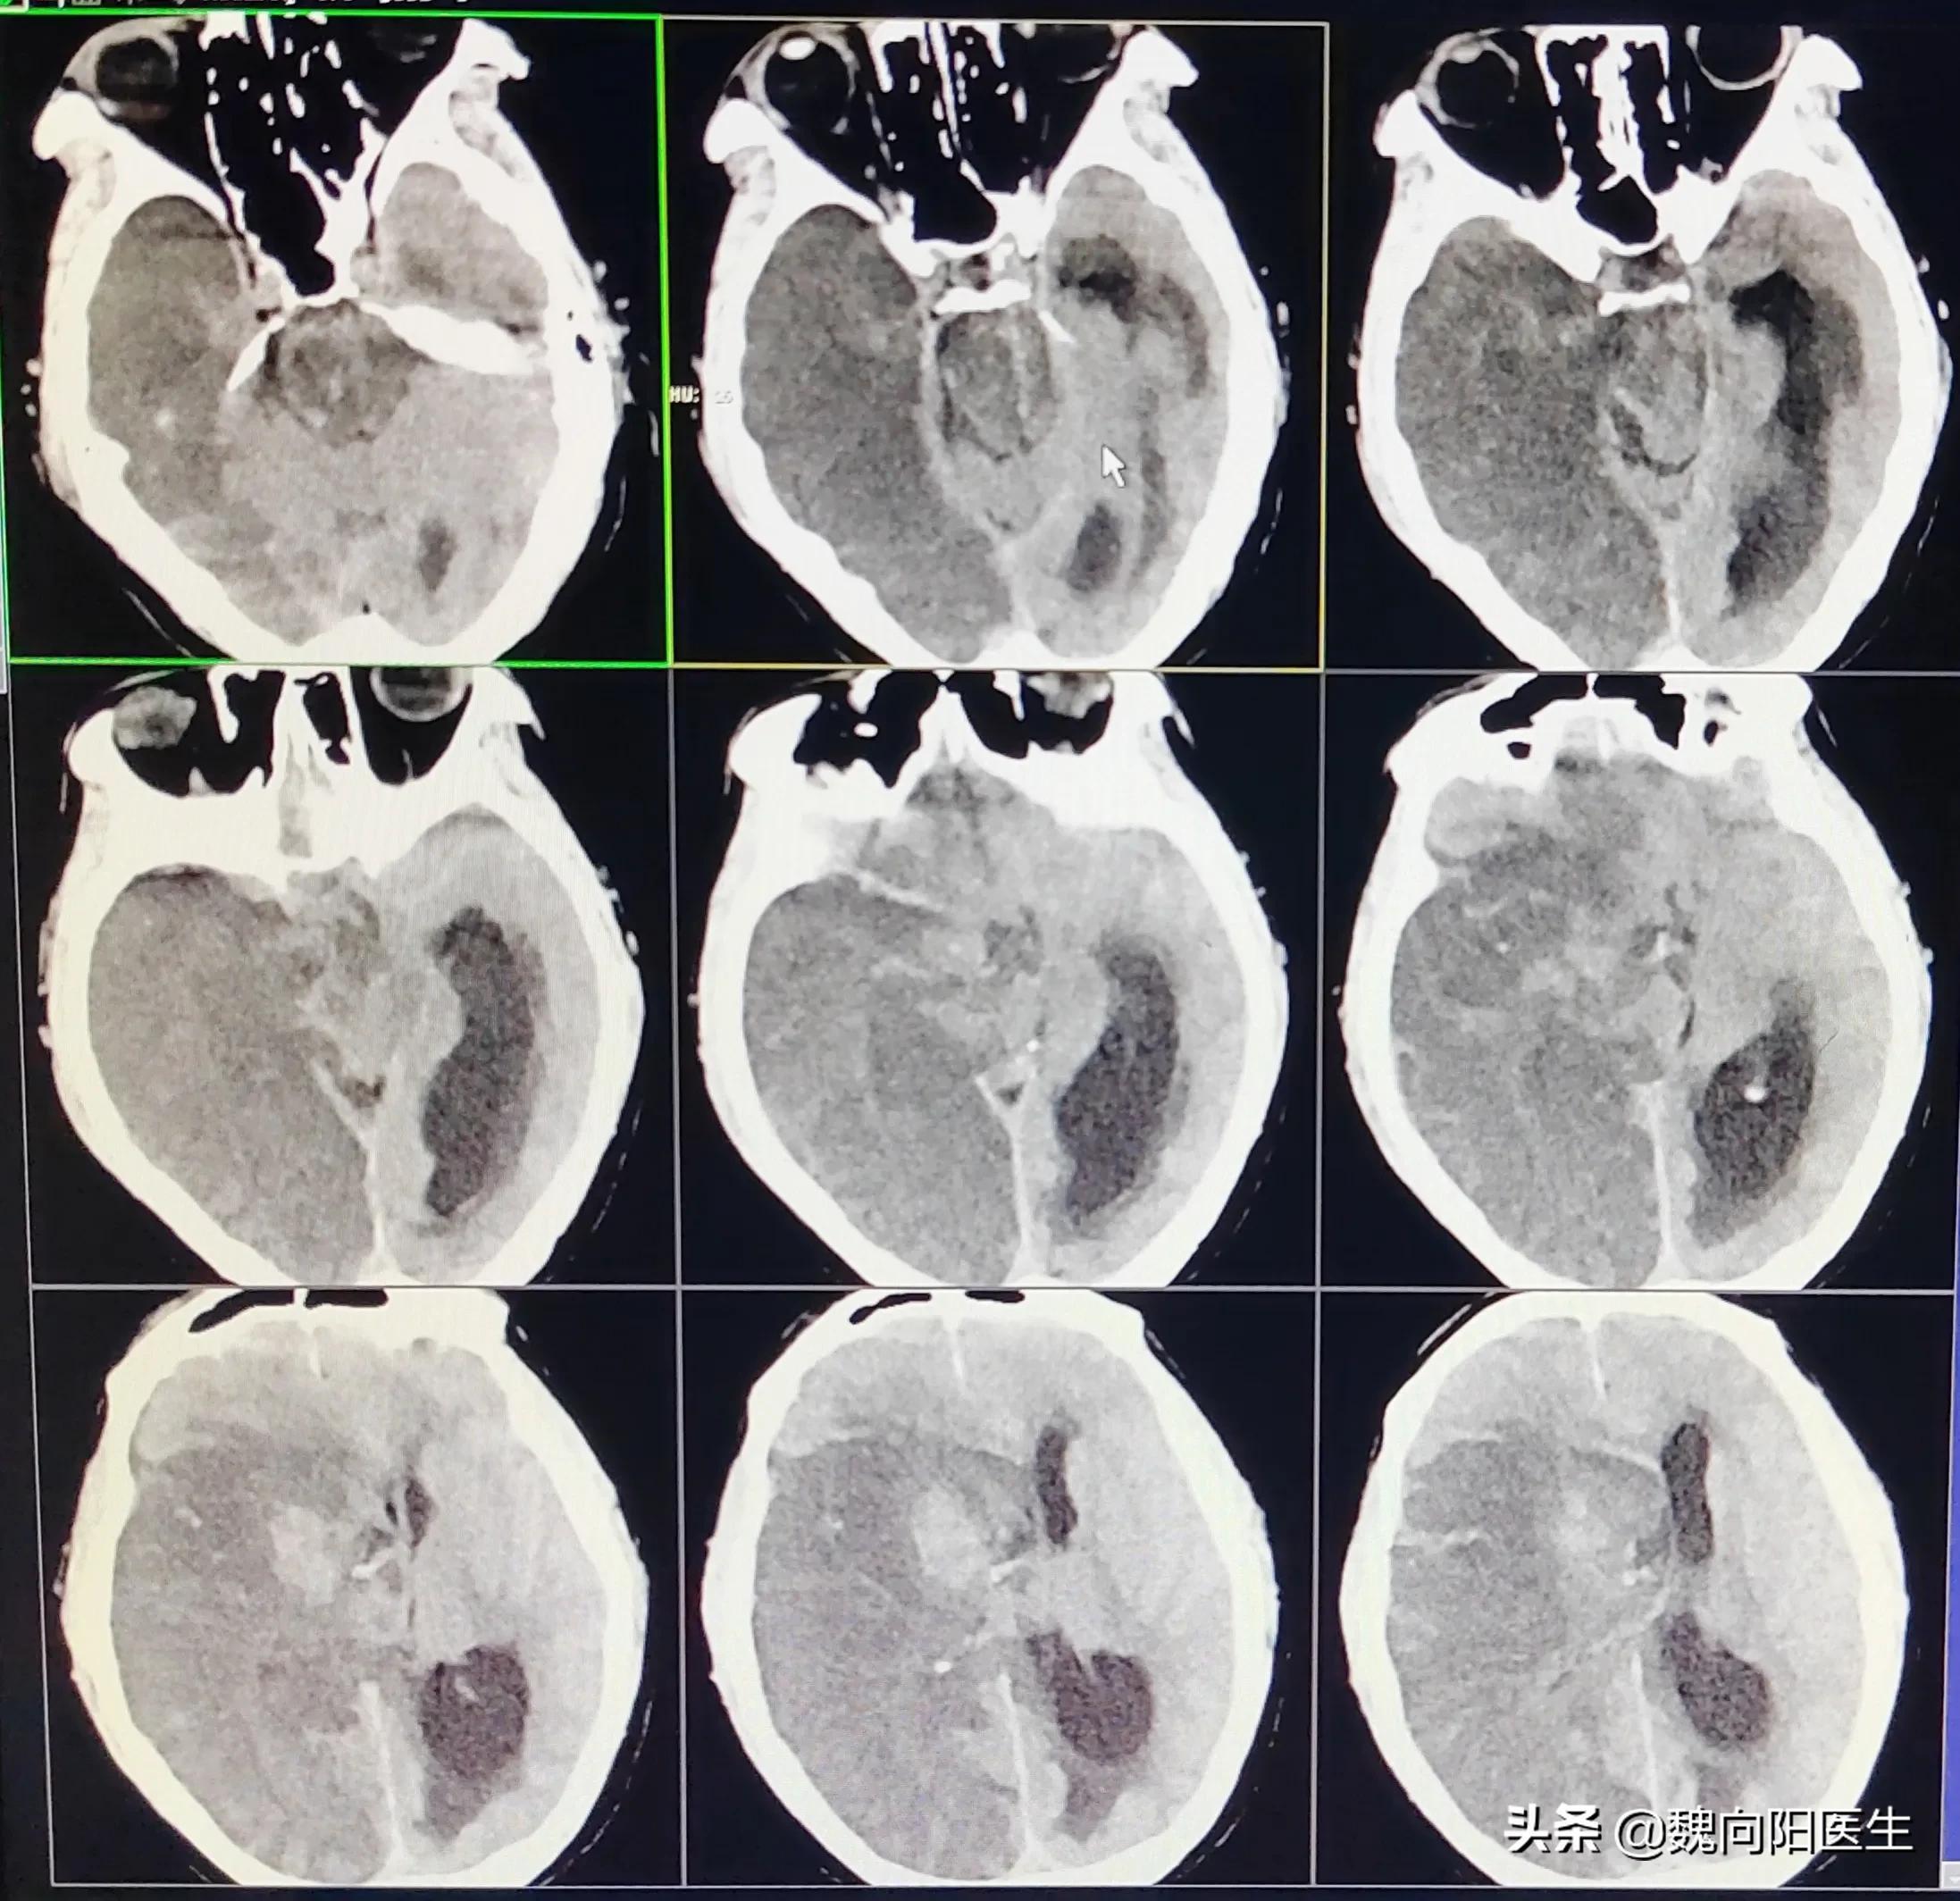

针对大动脉血栓形成的患者,一般给予静脉溶栓药物效果很差,大血栓再溶开几率相当低,且梗死区域会明显增加梗死后再出血的风险。

对于大动脉栓塞引起脑梗死的患者,积极给予静脉溶栓治疗,不但溶开的概率很低,甚至会明显增加颅内出血的风险。

梗死后出血